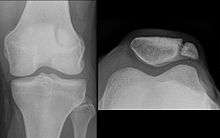

In this X-ray, an anatomical variation of the patella can be seen – the bipartate patella, in which the patella is split into two parts.

Emarginations (i.e. patella emarginata, a "missing piece") are common laterally on the proximal edge.[1] Bipartite patellas are the result of an ossification of a second cartilaginous layer at the location of an emargination. Previously, bipartite patellas were explained as the failure of several ossification centres to fuse, but this idea has been rejected. Partite patellas occur almost exclusively in men. Tripartite and even multipartite patellas occur.